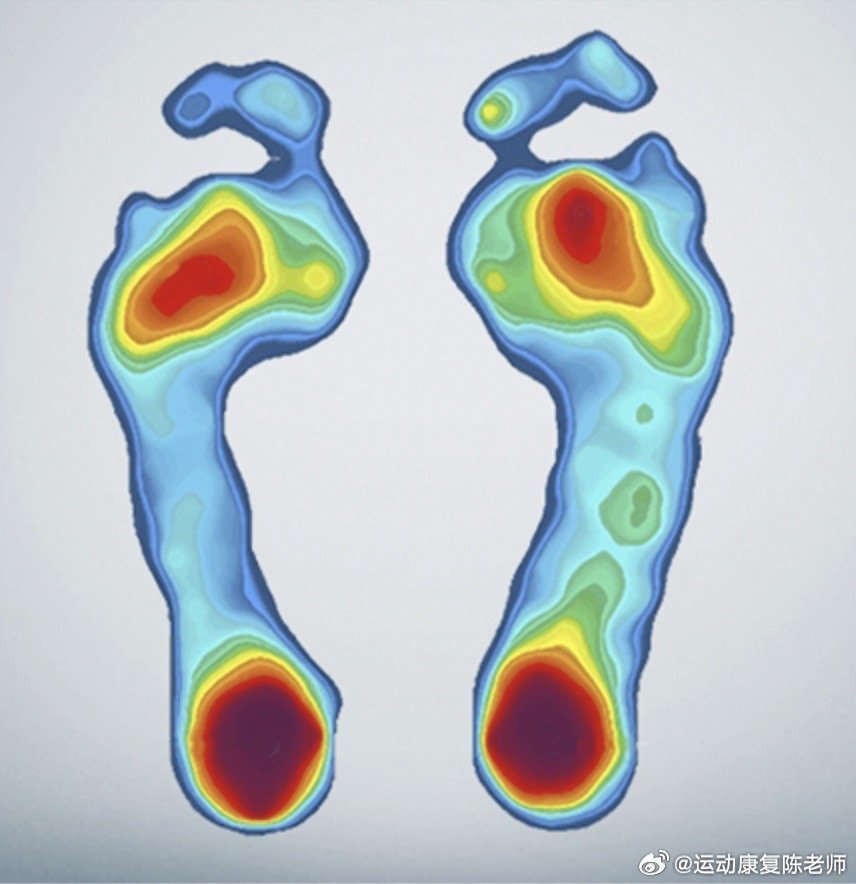

另一个方面,大脚趾外侧或前脚掌出现胼胝(老茧)也是横弓塌陷的典型信号⚠️